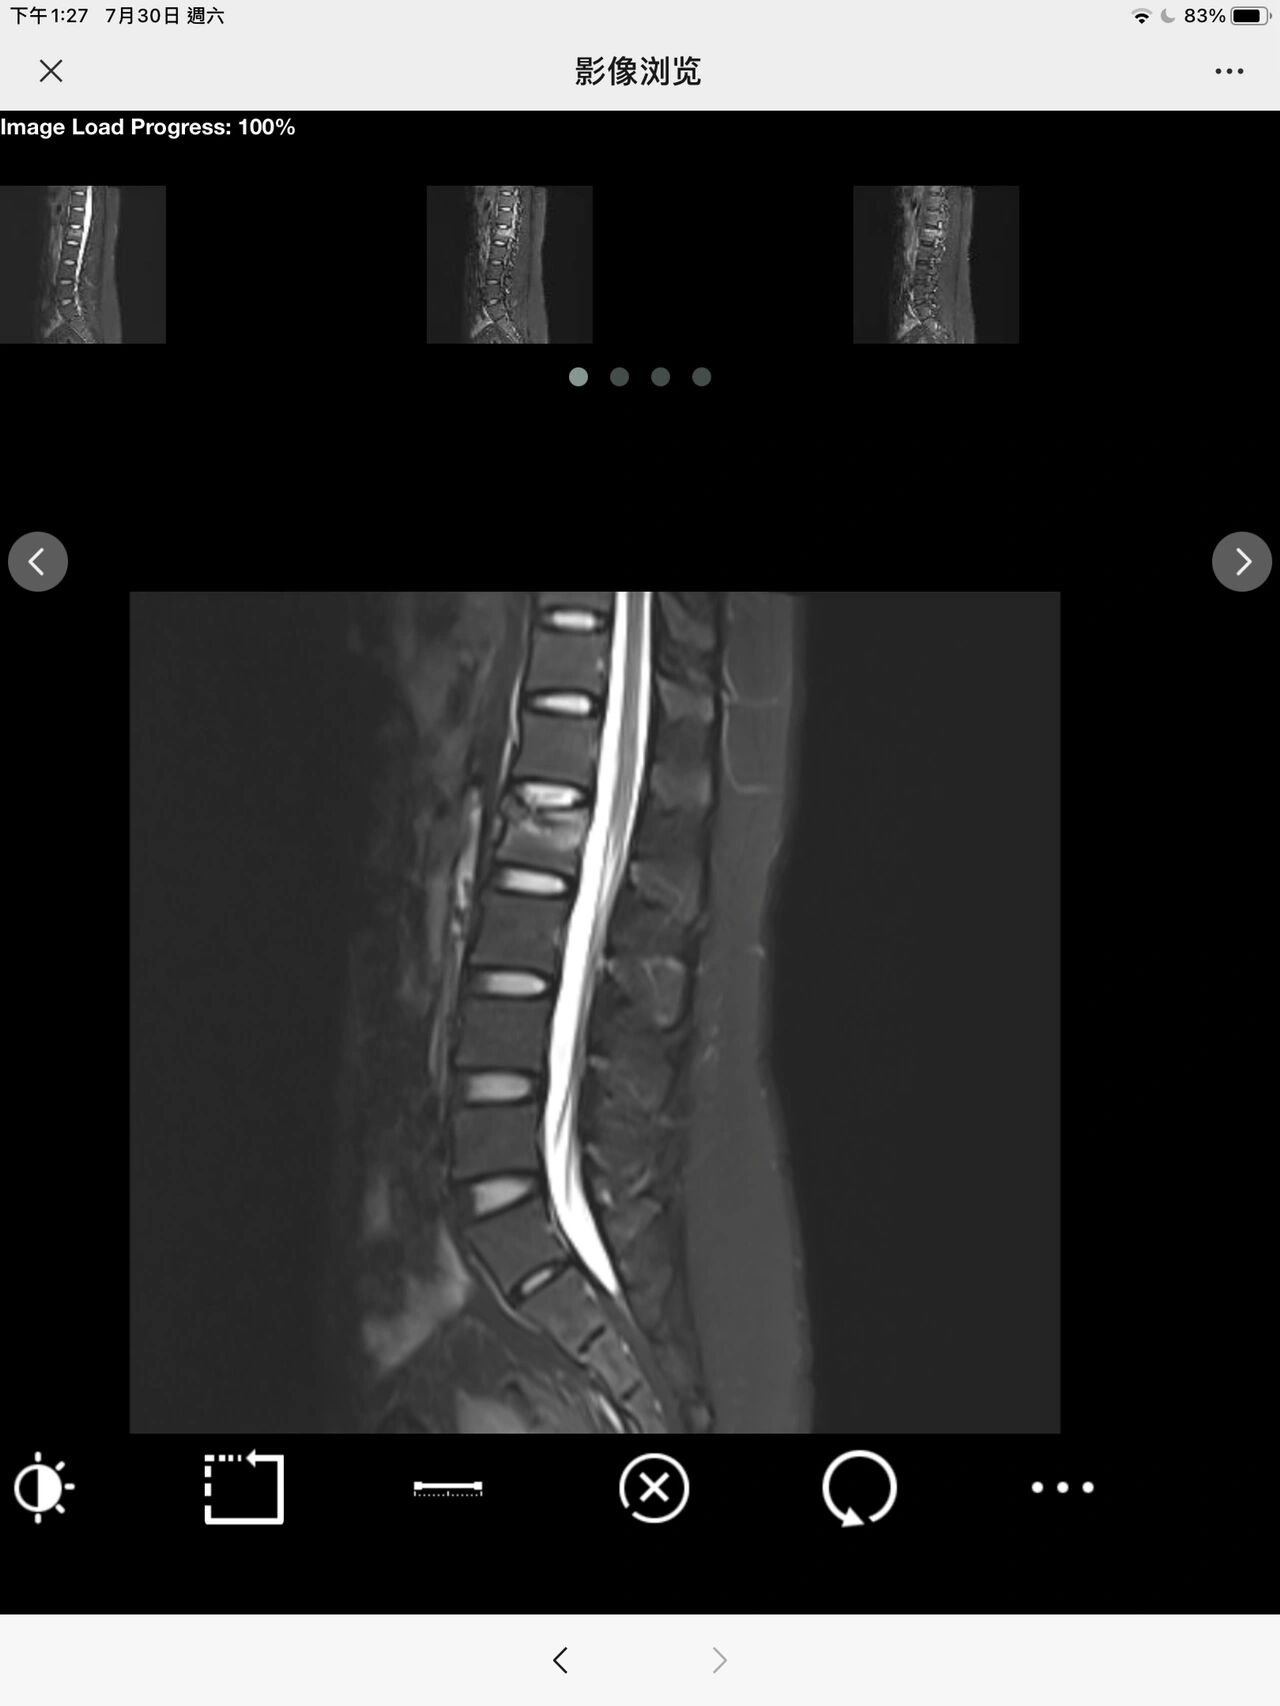

腰椎骨折是一种常见的脊椎损伤,根据其具体的类型和表现形式,可以进一步细分为多种类型其中,压缩骨折是腰椎骨折的一种类型这类骨折通常由于外力导致椎体压缩变形,常见于老年人或者骨质疏松患者腰椎骨折可以分为四大类,具体包括A类为压缩性骨折,B类为爆裂性骨折,C类为安全带骨折,D类为骨折脱位。

压缩性骨折是指腰椎的骨头在受到外力压力作用下,由于骨质疏松病变,导致骨体呈纵向被压扁而发生的一种骨折改变以下是关于压缩性骨折的详细解释发生部位压缩性骨折一般多发生在人的腰椎部位,尤其以胸腰段多见发生原因主要原因是腰椎骨头存在骨质疏松病变,这使得骨头在外力作用下容易发生压缩性改变。

腰椎压缩性骨折是指胸腰椎椎体受到外力后发生压缩性改变的一种骨折以下是关于腰椎压缩性骨折的详细解释成因创伤所致腰椎压缩性骨折多由外部创伤引起骨质疏松好发于患有骨质疏松的老年人,因为他们的骨质量骨密度骨强度下降,无法承载过度的暴力冲击轻微的损伤,如乘车颠簸或平地坐倒,都。

压缩性骨折是指椎体受到外力作用后发生高度下降的一种骨折类型,通常发生在腰椎以下是关于压缩性骨折的详细解释定义压缩性骨折,特别是腰椎压缩骨折,是指椎体受到外力作用后,其高度发生明显下降的骨折现象成因分类高能量损伤如摔伤车祸伤以及高处坠落伤等,这些外力作用巨大,导致的椎体压缩通常。